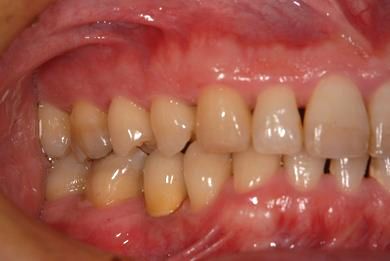

| 性別/年齢 | 男性 / 37歳 | ||||||||||||||||||||||||||||||||

| 主訴 | 前歯(2本)の欠けの治療 | ||||||||||||||||||||||||||||||||

| 治療方針 | 右下欠損部分をインプラント治療にて、機能的・審美的回復を行う。 | ||||||||||||||||||||||||||||||||

| 治療内容 | インプラント1本、メタルボンドセラミッククラウン1本 | ||||||||||||||||||||||||||||||||

| 総治療費 | 252,000円 | ||||||||||||||||||||||||||||||||

| 治療期間 | 7ヶ月 |